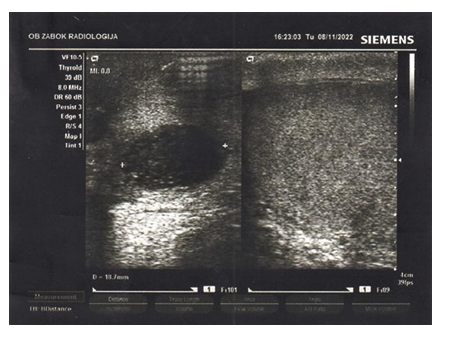

A 63-year-old patient presented to the urology department in September 2022 with a right testicular mass. He reported lifting heavy objects one month earlier. Past medical history included diabetes mellitus, obesity and arterial hypertension. The palpated scrotal mass was compared to the size of a goose egg. Ultrasound performed the same day resulted in a clinical diagnosis of hydrocele caused by trauma.

Postoperative ultrasound showed a smaller hematoma in the right testicle at the site of the previous operation (Figure 3.)